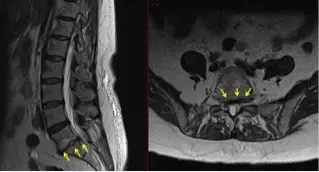

Diagnosis: degenerative disc disease

An MRI and CT of the lumbar spine showed severe degenerative disc disease at the L5-S1 level. “The collapsed and bulging disc was causing spinal canal, lateral recess and neuroforaminal stenosis with S1 nerve root impingement,” says Yen.